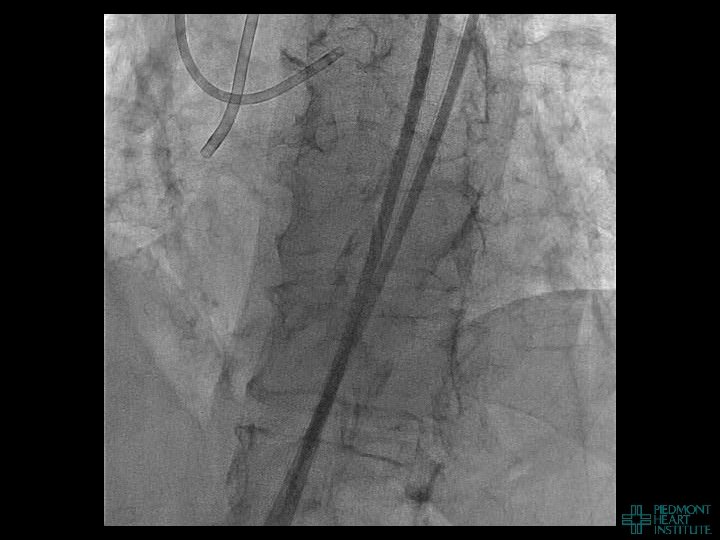

Case Example 3